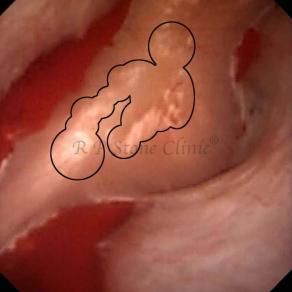

The Below Images Show Small Stones attached to the Renal Papillae.

These images are taken as snap shots from the video recording of RIRS Surgery done at our hospital. These are Randall’s Plaques seen with Digital FLEX XC & Digital FLEX XC S. The cream or whitish patches are seen on the tips of RENAL PAPILLAE as seen in images below.